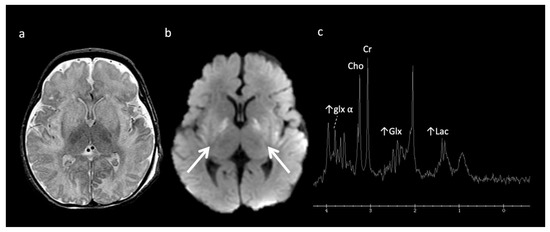

The most well-known and recognized pattern is Leigh syndrome (Figure 3) with symmetric deep grey nuclei and/or brainstem involvement on MRI [3]. Leigh syndrome may be due to a broad range of genetic variants in either nuclear or mitochondrial DNA.

Figure 3.

Leigh syndrome in a 10-year-old male with progressive right upper extremity weakness and left leg pain. (a) Axial T2WI shows T2 hyperintense necrotic lesions in the lentiform nuclei (arrows). (b) SV-MRS (short TE) over the basal ganglia shows increased Lac at 1.3 ppm consistent with anaerobic metabolism (indicating active on chronic disease, given the MRI appearance) and reduced NAA.

Mitochondrial encephalopathy with lactic acidosis and stroke-like episodes (MELAS) (Figure 4) may also have suggestive imaging features, with patients having non-vascular territorial metabolic stroke-like episodes [3]. Similar to MELAS, POLG-related mitochondrial disorders often cause nonterritorial cortical/subcortical edema/injury; however, perirolandic parenchyma and thalami tend to be more preferentially affected [19].

Figure 4.

Eleven-year-old male with new onset seizures and history of multiple stroke-like episodes attributed to mitochondrial encephalopathy, lactic acidosis, and stroke-like episodes (MELAS). (a) Axial T2WI and (b) axial DWI at the level of the midbrain show nonterritorial cortical/subcortical edema/swelling in the left occipito-temporal region involving both middle and posterior cerebral artery territories consistent with acute metabolic injury (white arrows). Volume loss, T2 prolongation, and facilitated diffusion consistent with encephalomalacia from old metabolic injury is noted in the right occipito-temporal region (red arrows).